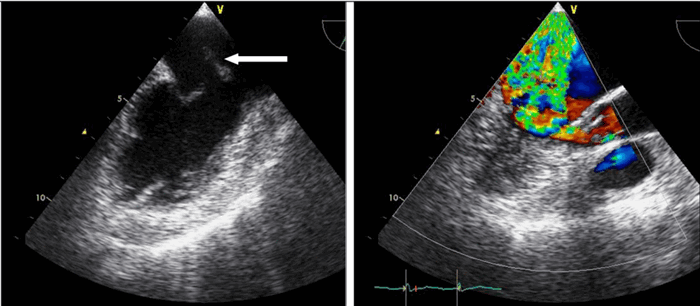

ВОЗМОЖНОСТИ СТРЕСС-ЭХОКАРДИОГРАФИИ В ДИАГНОСТИКЕ ЖИЗНЕСПОСОБНОГО МИОКАРДА У БОЛЬНЫХ ИШЕМИЧЕСКОЙ БОЛЕЗНЬЮ СЕРДЦА

Обсуждают основные методы диагностики жизнеспособного миокарда у больных ишемической болезнью сердца. Приводят сведения о современных возможностях стресс-эхокардиографии и тканевой Допплер-эхокардиографии для выявления жизнеспособного миокарда.

57. Madler C., Payne N., Wilkenshoff U. Non-invasive diagnosis of coronary artery disease by quantitative stress echocardiography:optimal diagnostic models using off-line tissue Dopplerin the MYDISE study. Eur Heart J 2003;24:1587-94.

58. Cain P., Baglin T., Case C. et al. Application of tissue Doppler to interpretation of dobutamine echocardiography and comparison with quantitative coronary angiography. Am Coll Cardiol 2001;87:525-31.

59. Miyatake K., Yamagishi M., Tanaka N. et al. New method for evaluating left ventricular wall motion by color-coded tissue Doppler imaging: in vitro and in vivo studies. J Am Coll Cardiol 1995;25:717– 724.

60. Tsutsui H., Uematsu M., Shimizu H. et al. Comparative usefulness of myocardial velocity gradient in detecting ischemic myocardium by a dobutamine challenge. J Am Coll Cardiol 1998;31:89–93.

65. Voigt J.U., Exner B., Schmiedehausen K. et al. Strain-rate imaging during dobutamine stress echocardiography provides objective evidence of inducible ischemia. Circulation 2003;107:2120–6.

66. Hoffmann R., Altiok E., Nowak B. et al. Strain rate measurement by doppler echocardiography allows improved assessment of myocardial viability inpatients with depressed left ventricular function. J Am Coll Cardiol 2002;39;443-449.

67. Hanekom L., Jenkins C., Jeffries L. et al. Incremental Value of Strain Rate Analysis as an Adjunct to Wall-Motion Scoring for Assessment of Myocardial Viability by Dobutamine Echocardiography: Follow-Up Study After Revascularization. Circulation 2005;112;3892-3900.